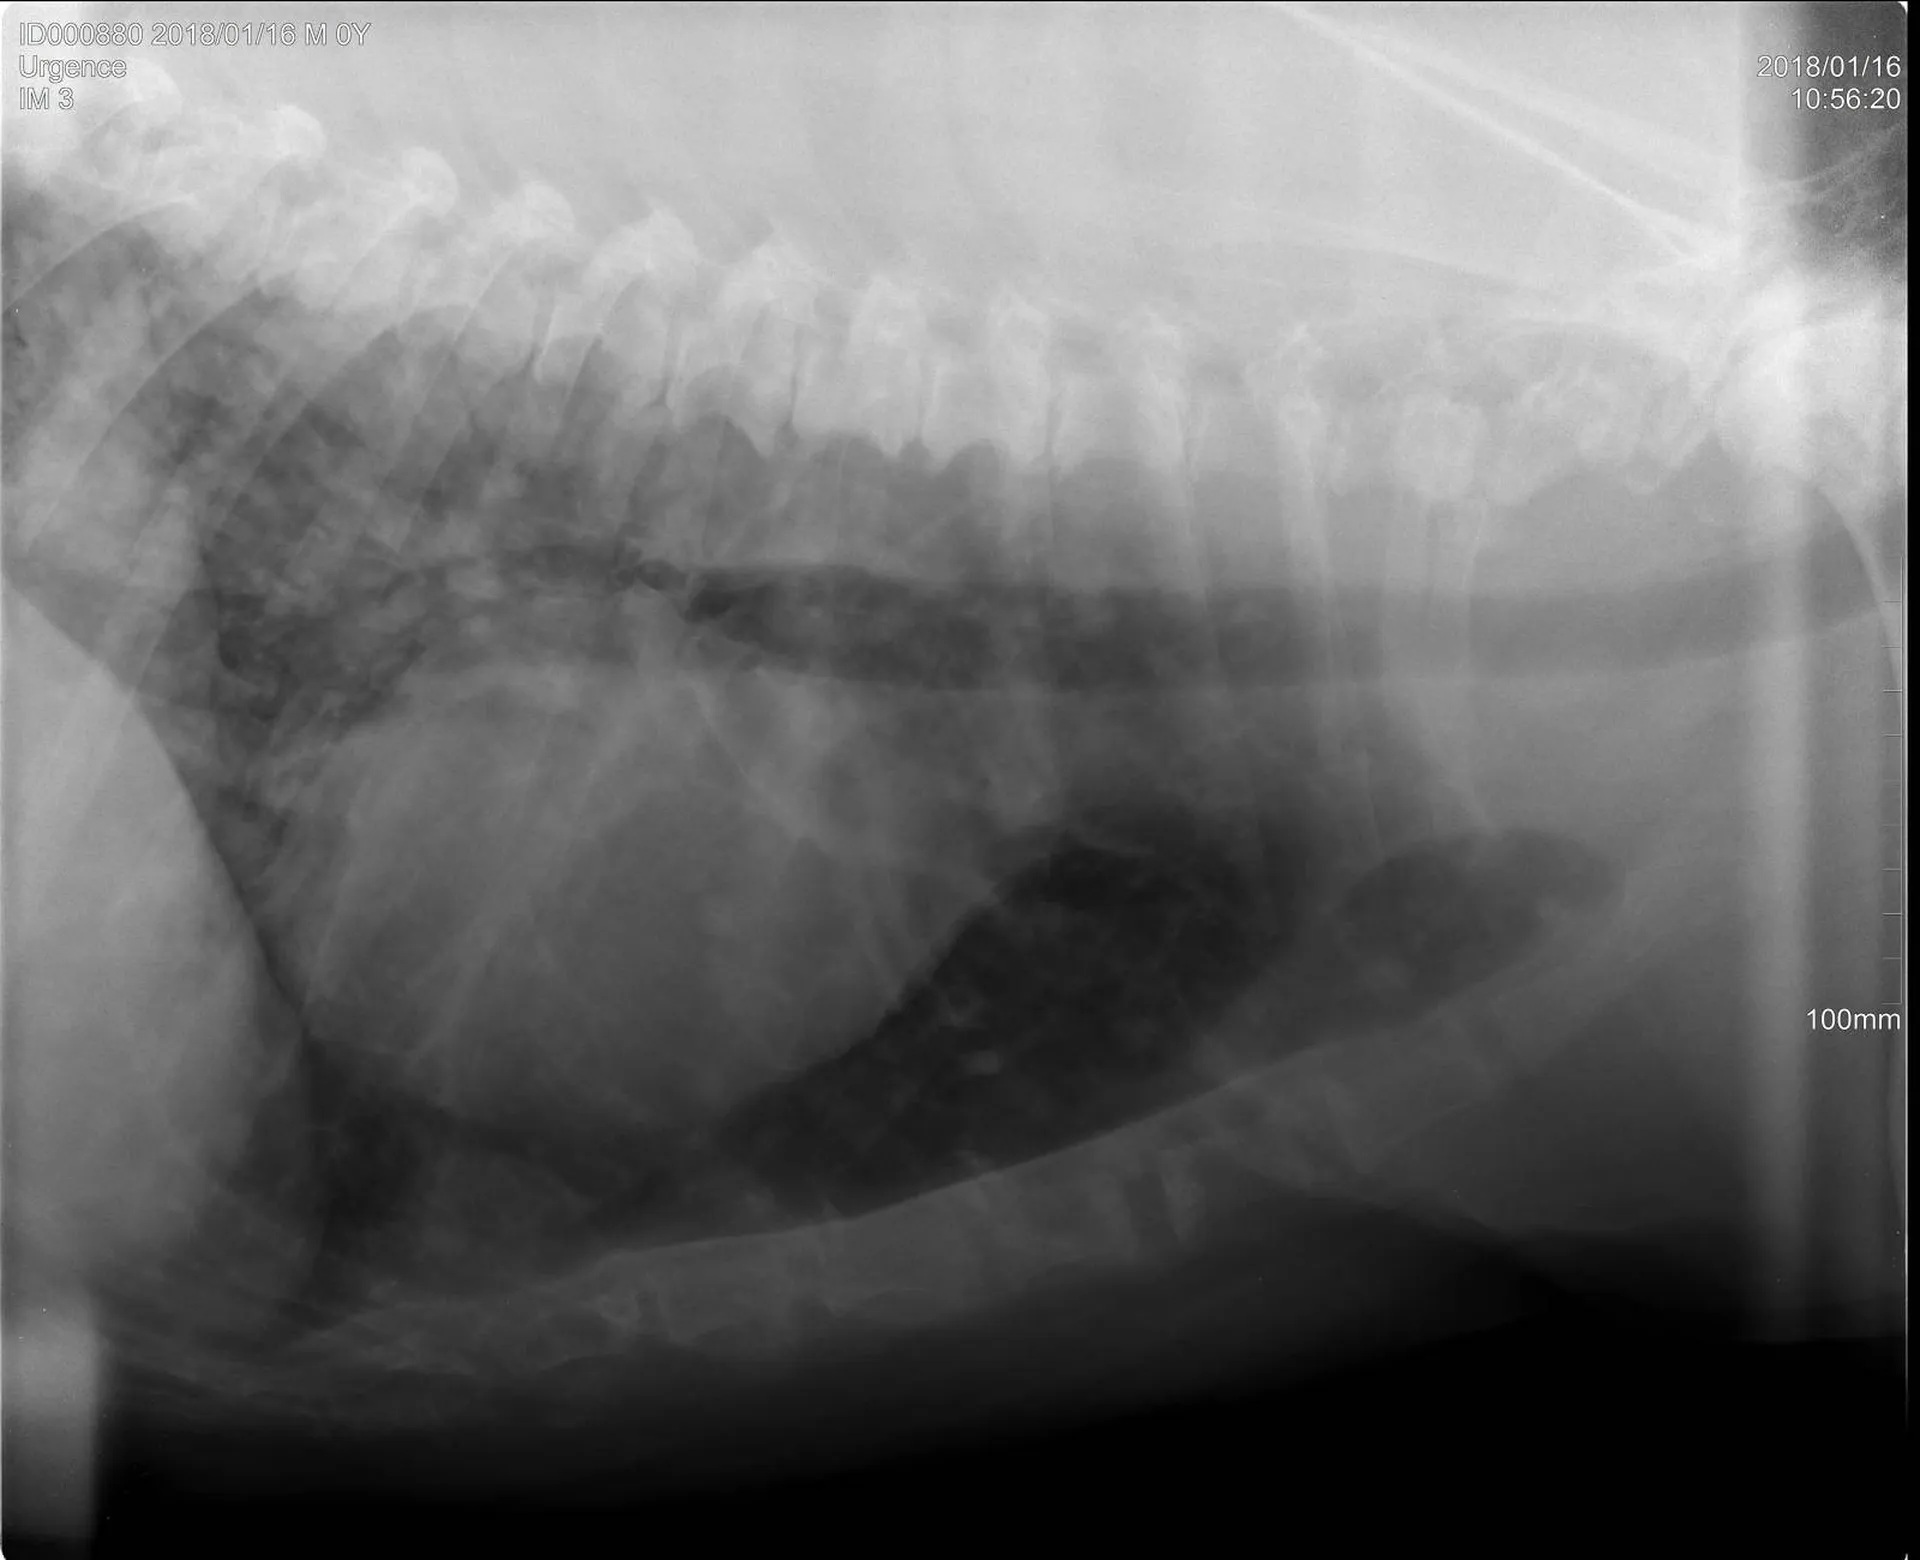

Une radiographie est un examen d’imagerie consistant à la prise de cliché au moyen d’un appareil à rayon X ceci afin de visualiser les différentes structures internes.

La radiographie reste indiquée dans de nombreuses affections, quelles soient respiratoires (radiographie cervicale ou thoracique), digestives (radiographie thoracique ou abdominale), locomotrices (membres, colonne), dentaires.

Votre chien, chat Nac est déposé sur la table de radiologie et différents clichés sont effectués dans différentes positions suivant la pathologie présentée.

Comme tout examen, il présente ses limites. Le principe de la radiographie étant l’utilisation du contraste (visualisation d’un tissu par rapport au tissu environnant et par rapport à sa radiodensité), certaines pathologies ne peuvent être que suspectées par radiographie mais nécessite d’autres examens (échographie, endoscopie, scanner, IRM).